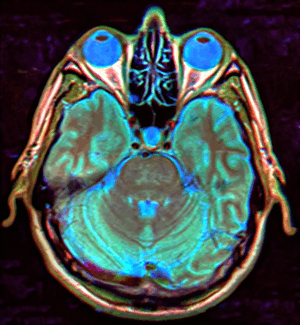

Empty sella syndrome (abbreviated ESS) is where the pituitary gland shrinks or becomes flattened,[1] filling the sella turcica, or "Turkish Saddle", with cerebrospinal fluid on imaging instead of the normal pituitary. ESS can be found in the radiological workup of pituitary disorders, or as an incidental finding when imaging the brain.

MRI scans are useful in evaluating ESS and differentiating it from other disorders that produce an enlarged sella.